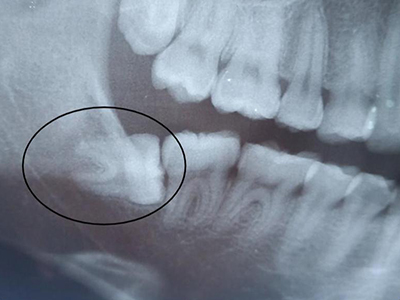

阻生牙是指由于邻牙、骨或软组织的阻碍而只能部分萌出或完全不能萌出,且以后也不能萌出的牙。引起牙阻生的成因,主要是由于颌骨缺乏足够的空间容纳全部恒牙。常见的阻生牙为下颌第三磨牙、上颌第三磨牙及上颌尖牙。

阻生牙主要原因是随着人类的进化,颌骨的退化与牙量的退化不一致,导致骨量相对小于牙量,颌骨缺乏足够的空间容纳全部恒牙。

对于阻生牙的处置需要首先明确阻生牙齿发育情况是否正常,对于由于早期外伤或其他原因造成发育异常,如牙根弯曲、短根等情况的阻生牙,还应根据患者的综合情况,决定牙齿是否保留。